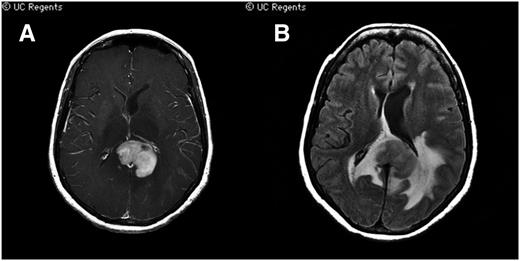

Because the presenting signs and symptoms of CNS and intraocular lymphoma are typically nonspecific, establishing a diagnosis may be difficult. A magnetic resonance–based examination of the brain, with gadolinium contrast, is the recommended first imaging test in diagnostic evaluation. In 95% of cases, there is homogenous enhancement localized to the tumor with rare necrosis, one of the radiographic features that help to distinguish CNS lymphomas from glioblastomas. Among immunocompetent patients with newly diagnosed PCNSL, lesions are solitary in 65% and multifocal in 35%. Cerebral hemisphere disease is most common (38%), followed by lesions within the thalamus/basal/ganglia (16%), corpus callosum (14%), ventricular region (12%), and cerebellum (9%) (Figure 2).46

Characteristic radiographic features of PCNSL on magnetic resonance imaging. (A) A T1 axial, postgadolinium image depicts a periventricular contrast-enhancing lesion with near-uniform contrast enhancement, vasogenic edema and mass effect, in displacement of the lateral ventricles. Lesional contrast enhancement using MRI is used for response assessment. (B) A flair signal abnormality demonstrates the extent of vasogenic edema. (Courtesy Soonmee Cha, MD, University of California–San Francisco).